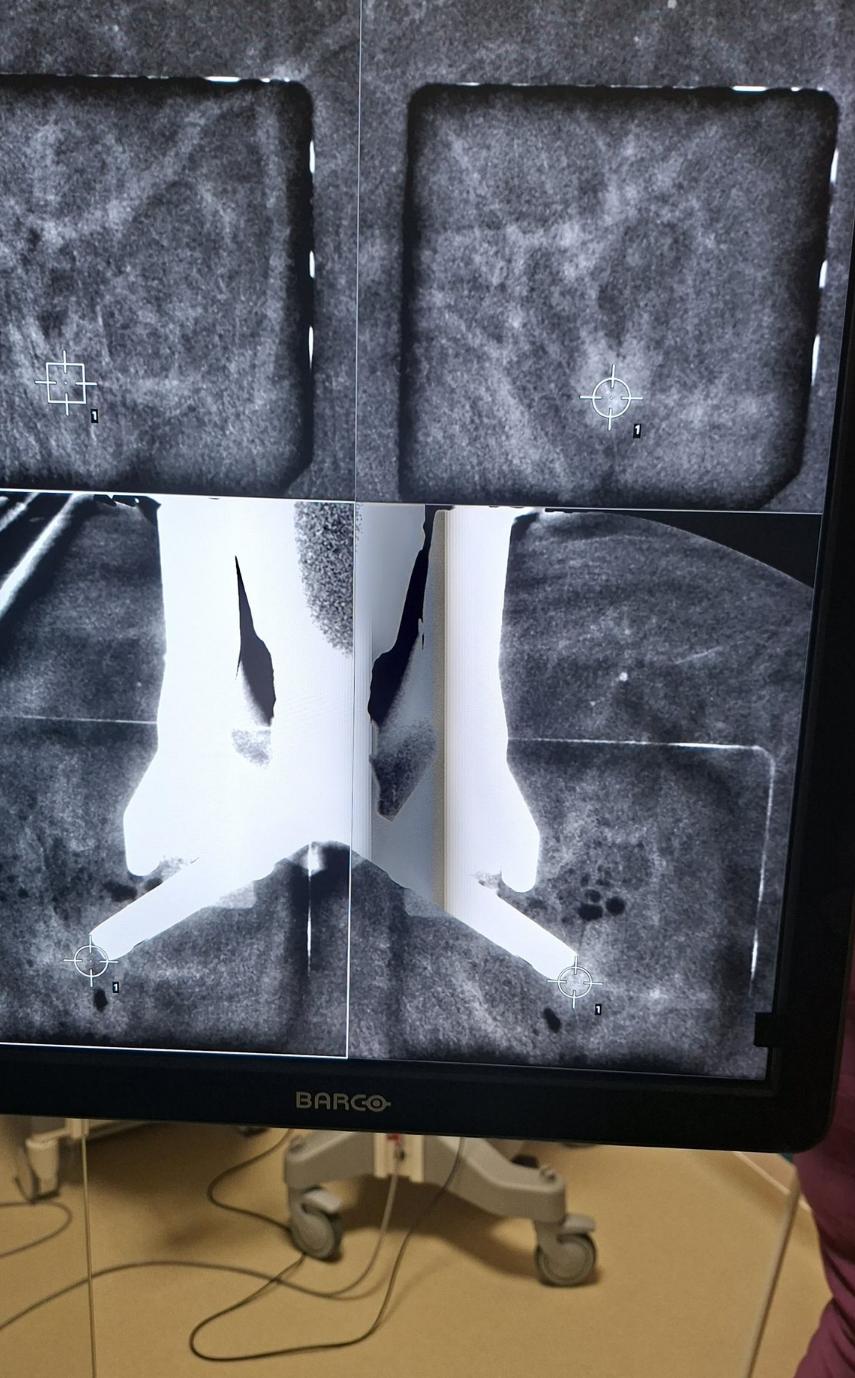

Medicul Carmen Lisencu a efectuat prima biopsie ghidată prin CEM (mamografie cu substanță de contrast), utilizând echipamentele moderne disponibile în cadrul institutului. Procedura reprezintă o alternativă mai accesibilă la biopsia ghidată prin RM (rezonanță magnetică), o metodă adesea mai costisitoare și mai greu de disponibil.

Biopsia ghidată prin CEM (Contrast-Enhanced Mammography) este o tehnică modernă de investigare care combină mamografia clasică cu administrarea unei substanțe de contrast pentru a evidenția zonele suspecte din sân. Aceasta este folosită în special atunci când leziunile nu sunt vizibile clar prin metode obișnuite, dar apar pe imaginile mamografice cu contrast.

Procedura este considerată o variantă adaptată a biopsiei stereotactice, fiind utilizată pentru a preleva probe din leziuni care pot fi observate doar pe imaginile CEM. În practică, metoda oferă o alternativă eficientă la biopsia ghidată prin RMN, fiind mai accesibilă și mai rapidă.